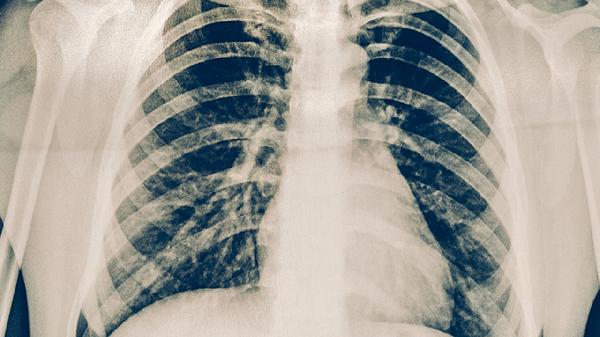

肺炎引起的心肌炎属于严重并发症,其危险性主要取决于心肌损伤程度和基础健康状况。肺炎并发心肌炎可能与病原体直接侵袭、免疫反应过度、毒素损伤、微循环障碍、电解质紊乱等因素有关,需通过心肌酶谱、心电图、心脏超声等检查评估病情。

重症肺炎引发的全身炎症反应可导致冠状动脉微血管痉挛,造成心肌缺血缺氧。临床表现为心电图ST-T改变合并心肌酶升高,需使用改善微循环药物如丹参多酚酸盐联合氧疗。